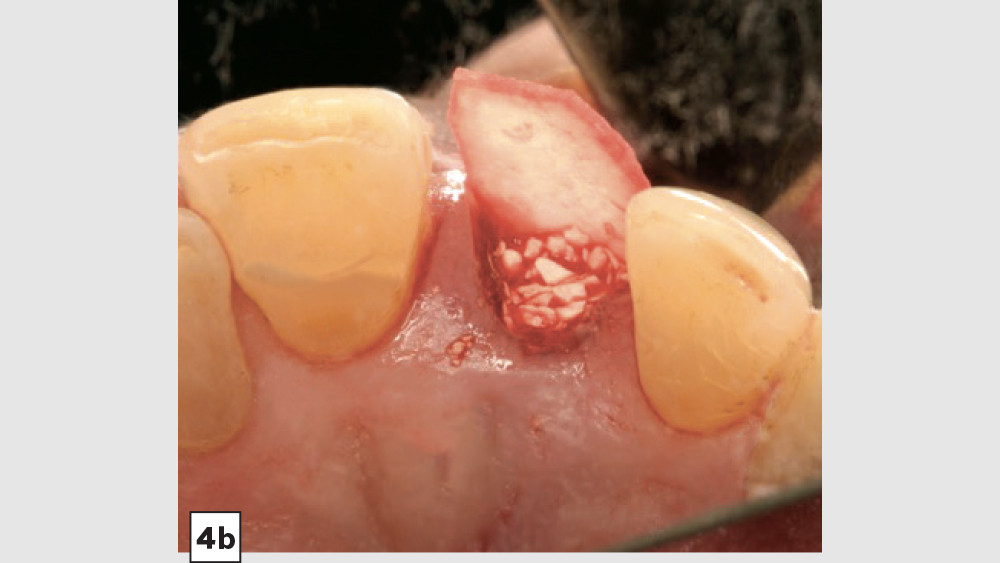

Five-Walled Socket Bone Grafting Technique (Figs. 1a–1d, 2a–2d)

1. Reflection: After extraction, a mucoperiosteal flap should not be reflected in most circumstances. However, a small subperiosteal pouch may be made around the margins of the extraction socket to allow for ease of membrane placement and suturing.

2. Preparation: The extraction socket should be free of soft-tissue remnants and bleeding should be present. If bleeding is not present, the remaining walls should be decorticated. Care should be exercised around adjacent teeth or vital structures. Bleeding from decortication will facilitate early vascularization and initiate the healing process.

3. Graft Material: The graft material (e.g., Newport Biologics Mineralized Cortico/Cancellous Allograft Blend) should be hydrated with sterile saline (0.9% sodium chloride) or platelet-rich fibrin (PRF) and then gently condensed into the socket. Small increments of material should be added into the socket, and a bone-packing instrument, such as the Bone Carrier and Spoon included with the 12-piece Newport Biologics Implant and Bone Grafting Instrument Kit (Glidewell Direct), should be utilized to condense the material to avoid air spaces (Fig. 3). Usually, when “push-back” of the material is present, the socket is packed sufficiently. Care should be exercised to avoid packing the graft material too densely, as this may interfere with angiogenesis and delay the healing process.

1. Membrane: A Newport Biologics Resorbable Collagen Plug should be cut in half and hydrated with 0.9% sodium chloride. The plug is compressed and placed over the socket, extending the collagen underneath the reflected subperiosteal pouch to increase retention.

2. Closure: Closure should be completed with a high-tensile suture material, such as polyglycolic acid (PGA) or PTFE, with a crisscross suture technique (Table 2). Care should be exercised to avoid suturing through the membrane. Gut sutures (plain, chromic) should be avoided, as they have a compromised tensile strength and will increase the probability of bone graft and membrane loss.